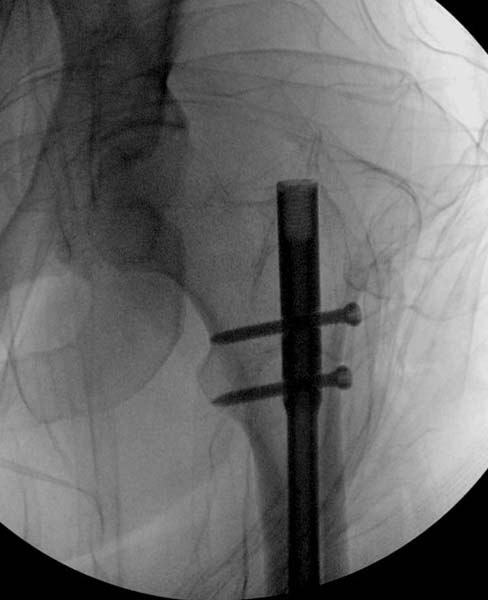

Остеосинтез бедра не стали делать из-за множественных переломов ребер с ушибом грудной клетки и поэтом у закончили фиксацию бедра наружным фиксатором.

Около 11.00 вечера больная переведена в реанимацию, без сознания, но стабильная.. На третьий день провели стабилизацию перелома бедра антеградным остеосинтезом.

Закрытый БИОС решает множественные проблемы связанные с лечением переломов, но проблема дистальной блокировки без рентгена до сих пор остается нерешенной. Рекламированные производителями приспособления для дистальной блокировки из-за различной кривизны кости не эффективны или стоит очень дорого (Smith&Nephew SureLock). Задержка операции из-за блокировки не всегда удовлетворяет, и многих вынуждает искать альтернативные методы фиксации. С результатами таких действий, остеомиелитом и несращениями, встречаемся в ежедневной жизни..

Для решения проблемы дистальной блокировки компания DigiMed недавно предложила систему блокировки без рентгена. Пока в стране только два набора и только для антеградных гвоздей, но компания работает над созданием устроиства для других гвоздей тоже..

Результат первых случаев показала отсутствие разницы между занятиями на муляжах, а также Workshop и с удивительной точностью вывел латерально над кожей специальное сверло. Дальше по сверлу тонкий направитель и проводится сверление каннюлированным сверлом....